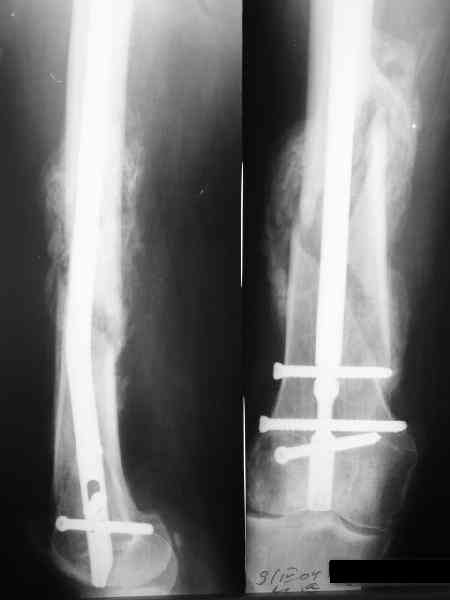

27 марта выполнено удаление блокирующих винтов (сломанный винт пришлось высверливать цапфен-бором), сломанного штифта (дистальный фрагмент удален через канал, образованный разверткой из коленного сустава - image 4),

рассверливание костно-мозгового канала, реостеосинтез штифтом UFN (при проведении штифта в дистальном отломке мы использовали поляризующий винт, диаметр штифта 10 мм). После операции в связи гемартрозом дважды (на 1 и 3 сутки) выполняли пункцию коленного сустава. Сейчас признаков скопления жидкости в полости сустава нет. Послеоперационные рентгенограммы - images 5, 6, 7.